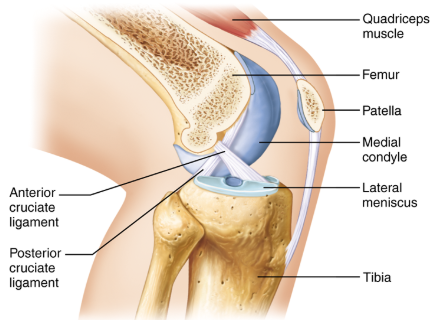

What is the tibiofemoral joint?

The knee joint.

What is the joint shown here?

The tibiofemoral joint.

What is the joint shown here?

The tibiofemoral joint.

What ligament is shown here?

Anterior cruciate ligament.

What ligament is shown here?

Anterior cruciate ligament.

What does the anterior cruciate ligament prevent?

The anterior cruciate helps prevent anterior sliding of the tibia.

What ligament is shown here?

Posterior cruciate ligament.

What ligament is shown here?

Posterior cruciate ligament.

What does the posterior cruciate ligament prevent?

The posterior cruciate prevents forward sliding of the femur or backward displacement of the tibia.

What is the highlighted fibrocartilage?

Lateral meniscus.

What is the highlighted fibrocartilage?

Lateral meniscus.

What is the highlighted fibrocartilage?

Medial meniscus.

What is the highlighted fibrocartilage?

Medial meniscus.